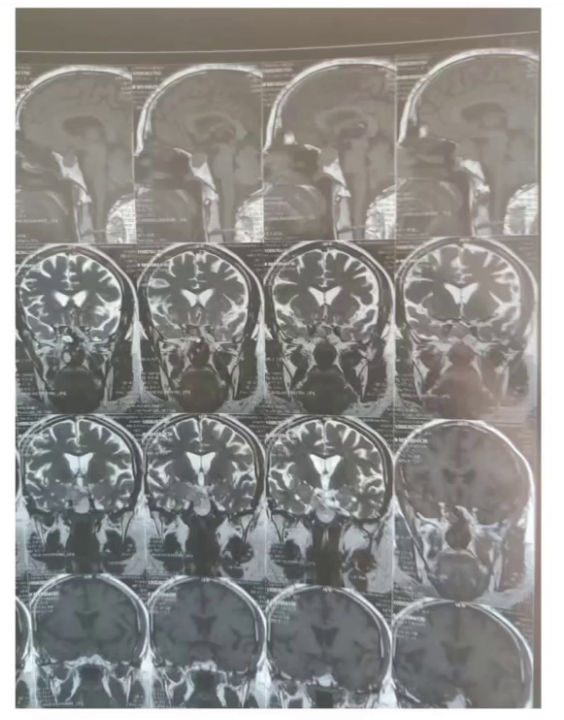

2022年5月垂体核磁平扫及增强:结合病史垂体瘤术后改变,现垂体右缘异常强化灶,与2019.4.15前片相比病变体积较前增大,请结合临床随诊。(增强扫描鞍区右缘可见稍低强化结节,矢状位测其范围约2.22cm×2.17cm, 右侧颈内动脉海绵窦段被包绕,垂体柄向左侧偏移,视交叉位置正常;左侧颈内动脉海绵窦段未见明显异常)。

2023年3月垂体核磁平扫及增强:1.结合病史垂体瘤术后改变,现垂体右缘异常强化灶,与2022.5.26前片相比病变体积较前增大。管状位测其大小约2.55cm×2.12cm,右侧颈内动脉海绵窦段被包绕。

2024年10月垂体核磁平扫及增强:鼻窦及鞍底骨质信号不连续,术区结构紊乱,呈术后改变,正常垂体形态消失,垂体右缘可见片状稍长T1混杂长T2信号,垂体柄向左侧偏移,增强扫描垂体右缘可见片状未强化区,冠状位较大层面测其大小约为0.81cm×0.67cm。